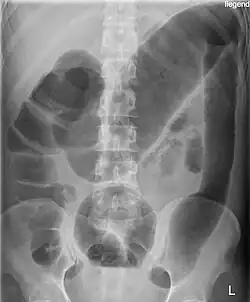

![]() Radiografía del abdomen de un paciente afecto de megacolon tóxico secundario a colitis ulcerosa. | ||

En medicina, el término megacolon se emplea para describir aquella situación en la que la región del intestino grueso denominada colon se dilata de forma anómala, produciéndose un aumento de su diámetro habitual. Puede deberse a numerosas causas, algunas de las más frecuentes son el megacolon agangliónico o enfermedad de Hirschsprung y el megacolon tóxico.[1]